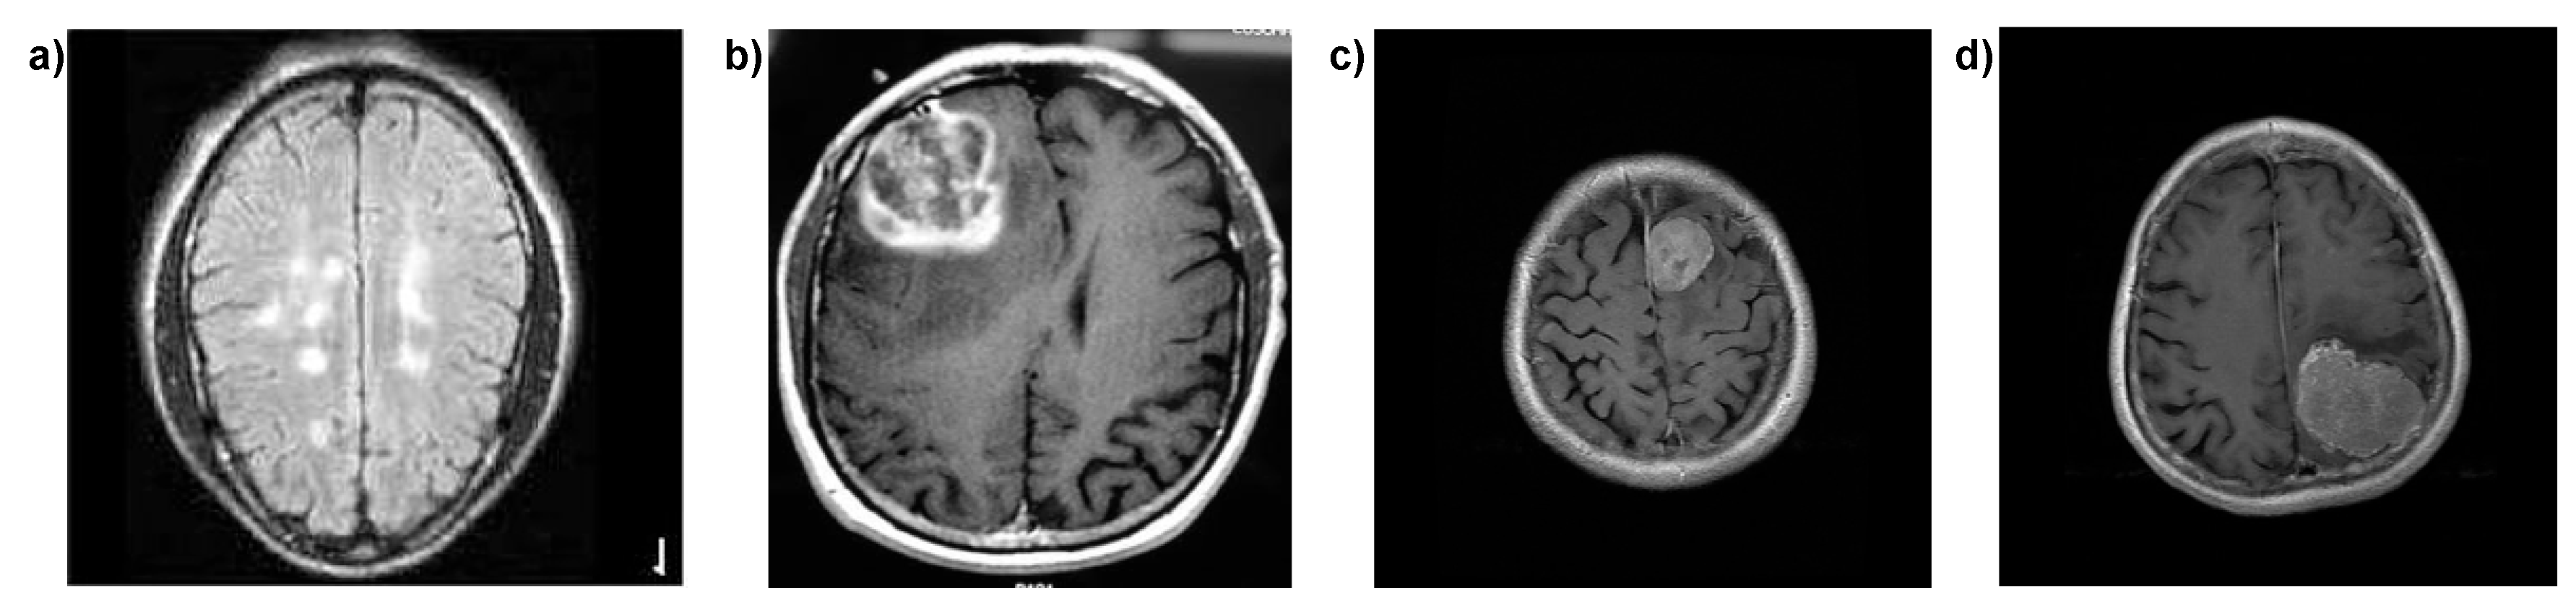

3.1. Dataset Description

3.2. Dataset Preprocessing